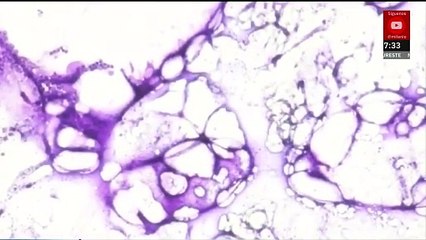

El Sistema Nacional de Vigilancia Epidemiológica ha emitido una alerta por el aumento de casos de #TosFerina, una infección respiratoria altamente contagiosa causada por la bacteria Bordetella pertussis, la cual es especialmente peligrosa para mujeres embarazadas, adultos mayores, bebés y niños que no están vacunados.